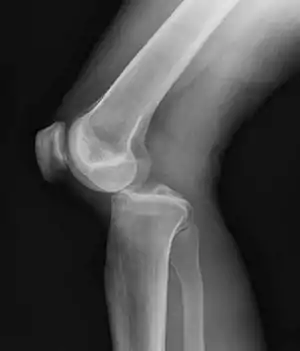

Plain X-rays, CT scan, ultrasonography, or MRI may help with the diagnosis.[2][10] Findings on X-ray that may be useful among those who have already reduced include a variable joint space, subluxation of the joint, or a Segond fracture.[5]

They may be divided into five types: anterior, posterior, lateral, medial, and rotatory.[4] This classification is based on the movement of the tibia with respect to the femur.[10] Anterior dislocations are the most common, followed by posterior dislocations.[2] They may also be classified based on what ligaments are damaged.[2]